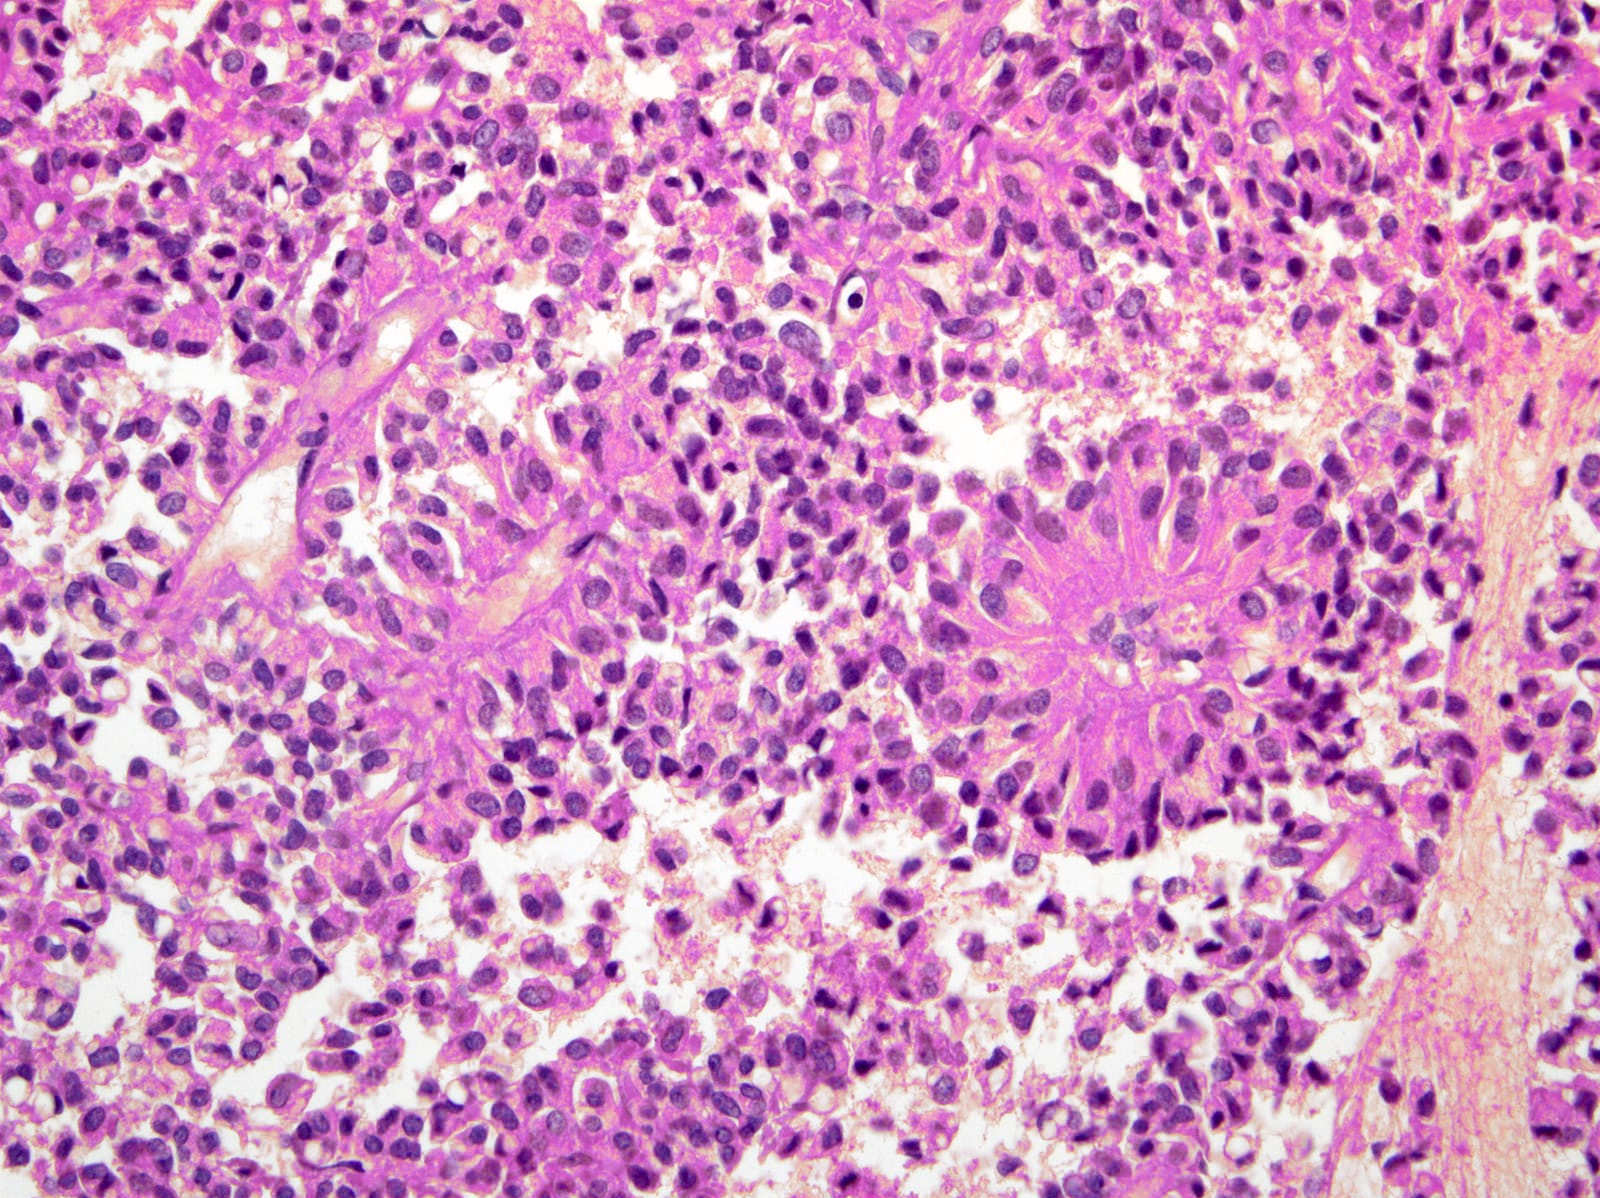

Microscopic (histologic) description

- Tumors are heterogeneous, with variable admixture of solid and pseudopapillary areas

- Solid areas are comprised of uniform cells admixed with capillary sized blood vessels

- Pseudopapillae are formed due to tumor cells getting detached from blood vessels forming fibrovascular stalks or rosette-like structures (Arch Pathol Lab Med 2020;144:829)

- Stroma usually shows various degrees of hyalinization or evidence of degeneration, such as hemorrhage, foamy macrophages, calcification and cholesterol clefts

- Tumor cells usually have a moderate amount of eosinophilic cytoplasm with intracytoplasmic hyaline globules (PAS+ and diastase resistant, positive for alpha-1-antitrypsin) and perinuclear vacuoles (Am J Surg Pathol 2011;35:981)

- Relatively uniform nuclei with finely textured chromatin, inconspicuous nucleoli and characteristic longitudinal grooves

- Variants include clear cell, oncocytic and pleomorphic

- Rare mitotic figures

- Although grossly well circumscribed, microscopic finding of infiltration to the surrounding pancreatic tissue is not uncommon

- Rare cases of highly aggressive behavior; histological features in those cases included diffuse growth pattern, extensive necrosis, significant nuclear atypia, high mitotic count (35 - 70/50 high power fields) or sarcomatoid features (Am J Surg Pathol 2005;29:512)

Microscopic (histologic) images

Contributed by Monika Vyas, M.D., Omid Savari, M.D. and Raul S. Gonzalez, M.D.